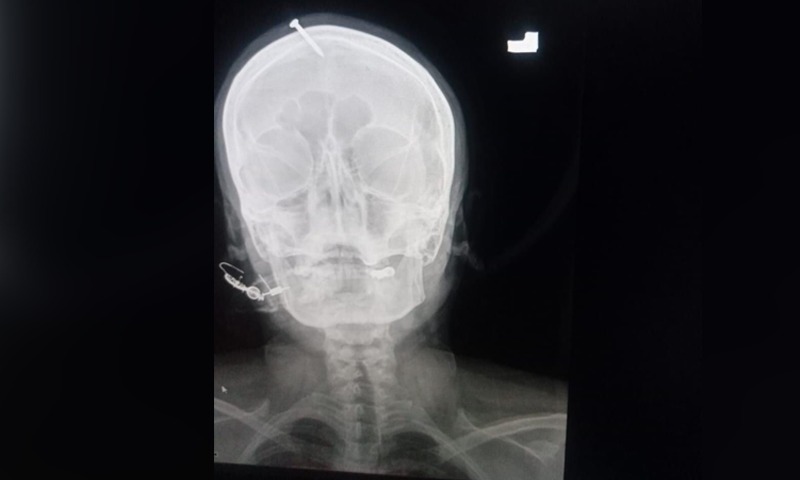

10/02/2022 16:49Đóng đinh vào đầu để chuyển giới tính thai nhi

Ảnh chụp X-quang cho thấy chiếc đinh dài 5 cm đã đâm xuyên qua đỉnh trán của người phụ nữ rồi xuyên qua não của cô ấy.

Ban đầu, người phụ nữ nói với nhân viên bệnh viện rằng cô đã tự đóng đinh vào đầu mình theo lời khuyên của một thầy lang chữa bệnh bằng đức tin, trước khi nói rằng chính ông ta mới là người thực hiện hành vi này. Tuy nhiên sau khi được các bác sĩ hỗ trợ để gỡ bỏ chiếc đinh, người phụ nữ đã ngay lập tức rời khỏi bệnh viện mà không ai biết.